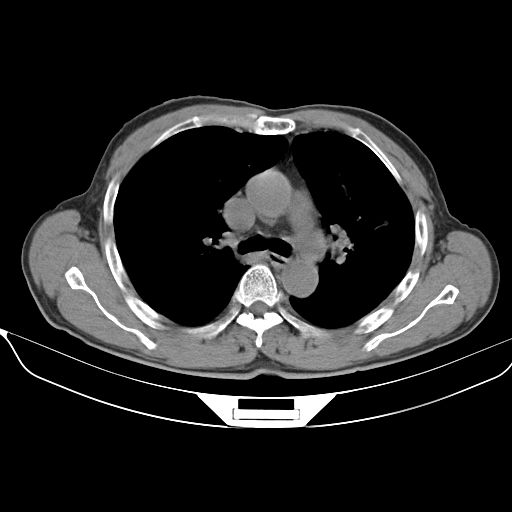

以下是引用心路寻觅在2010-3-1 10:23:00的发言:[br]1、考虑左肺上叶周围型肺癌[br]2、右上肺陈旧性病灶。[br][br][本贴已被 心路寻觅 于 2010-3-1 10:40:18 修改过]

以下是引用shuiyuan在2010-3-1 10:45:00的发言:[br]考虑左肺上叶中心型肺癌伴阻塞型炎症,邻近胸膜受侵。